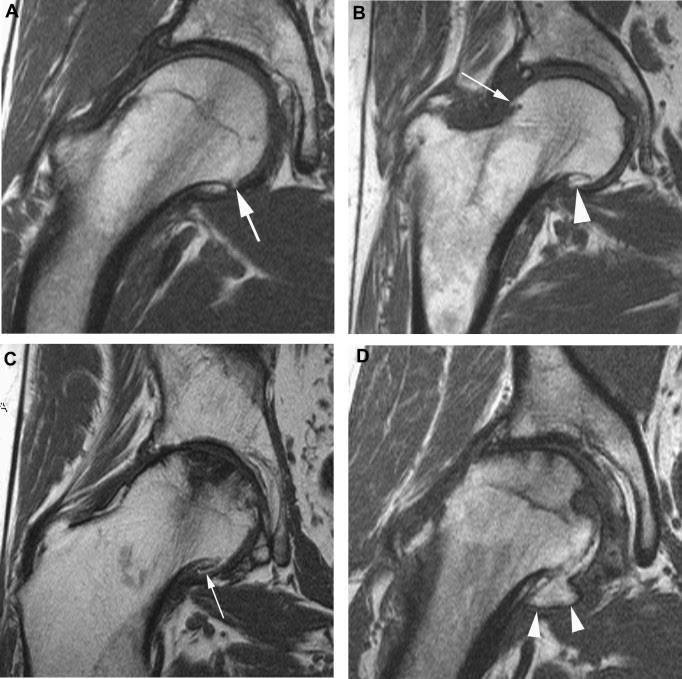

동위 원소 검사는 관절염이 있는 부위에 혈류가 증가하고 골 형성이 활성화되어 검사 상 짙은 음영을 관찰할 수 있습니다. 단순 방사선 사진에서 이상이 나타나기 이전인 가벼운 관절염도 진단이 가능하다는 특징이 있습니다. 자기공명영상(MRI)은 동반된 연부조직(내부 장기와 딱딱한 뼈 등을 제외한 우리 신체의 연한 조직. 근육, 인대, 지방, 섬유조직, 활막조직, 신경혈관 등)의 이상이나 관절 연골의 상태를 보는데 유용하고, 진단적으로 관절경을 시행하면 골 병변이 나타나기 이전에 연골의 변화와 상태를 관찰할 수 있습니다.

MRI

grade 0: normal

grade 1: inhomogeneous high signal intensity in cartilage (T2WI)

grade 2: inhomogeneity with areas of high signal intensity in articular cartilage (T2WI); indistinct trabeculae or signal intensity loss in femoral head and neck (T1WI)

grade 3: criteria of grade 1 and 2 plus indistinct zone between femoral head and acetabulum; subchondral signal loss due to bone sclerosis

grade 4: above criteria plus femoral head deformity